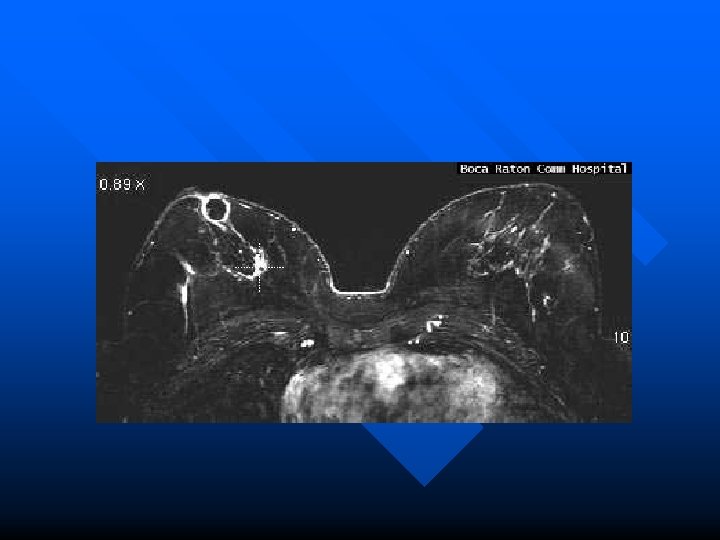

Example Case n n This 61 year old female presented with a dominant mass in the right breast with several other indeterminate lesions seen on mammography. Mammography CC view demonstrates three masses in the right breast, one behind the nipple and two others in its medial portion.

n MRI magnification maximum intensity projection (MIP) view of right breast demonstrates the same three masses with tumor bridging between them and extending toward the chest wall.

n MRI T 2 axial slice indicates cystic nature of subareolar mass.

n MRI subtraction and color images show rim enhancement around cystic mass.

n MRI image of color map of enhancement curves (kinetics of breast tissue) show intense early enhancement and rapid signal loss from the dominant mass (typical malignant characteristics).

n n n Enhancement curve from dominant mass. Final Pathology at mastectomy confirmed that the dominant mass represented infiltrating carcinoma with extension of intraductal carcinoma. The subareolar cystic mass represented encysted papillary carcinoma.